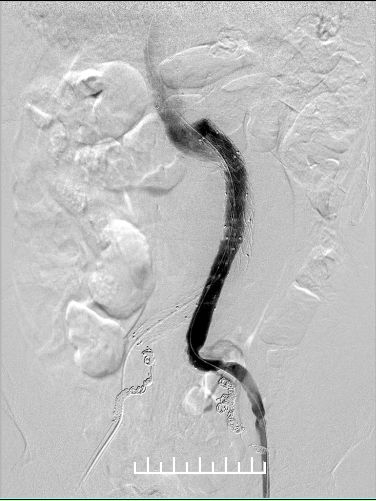

Ib型内漏(远端漏),需要处理

左右分别使用13.5*80、13.5*60mmFluency延长。左侧支架一定要越过髂动脉弯曲处,否则容易闭塞。此处可以看到左侧支架远端稍微有弯曲折叠。

仍然漏

不慌,还可以使用顺应性球囊扩张。

髂动脉硬化严重